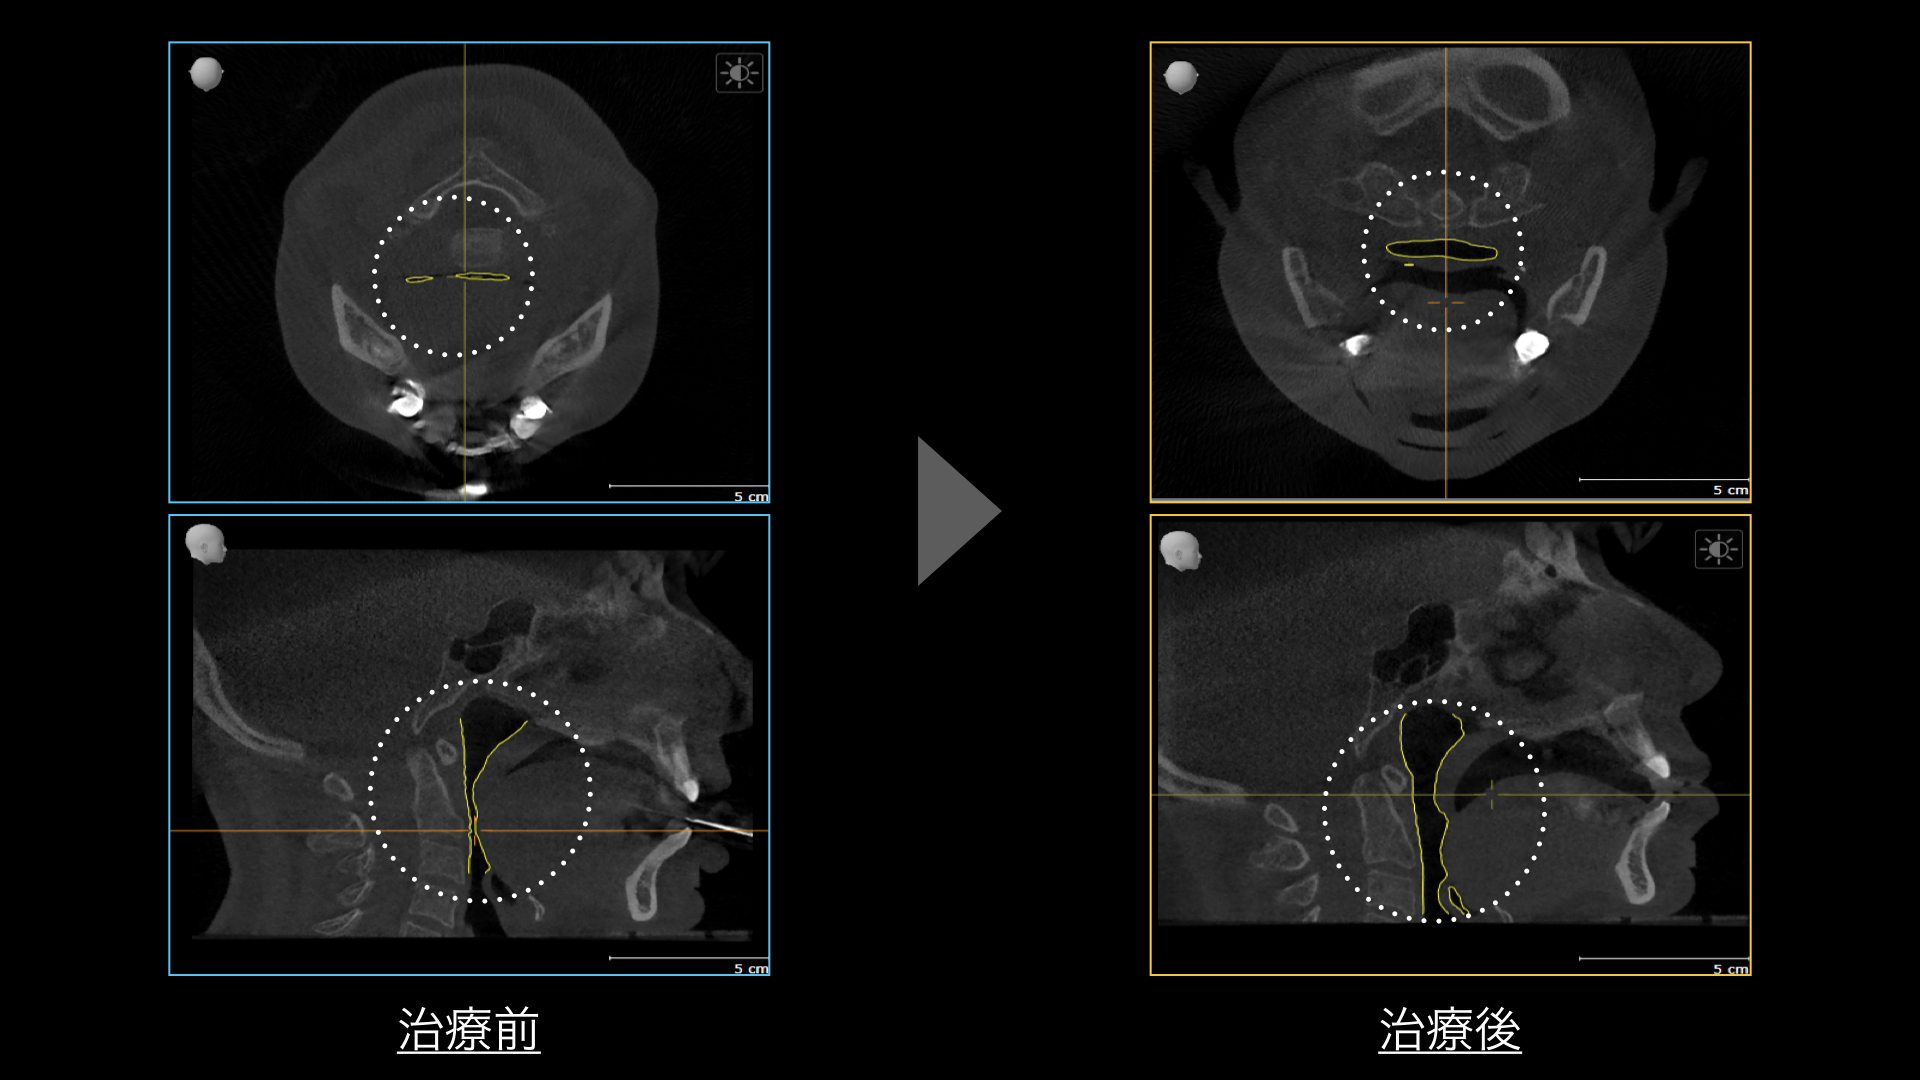

新時代の”歯を残す”歯周病治療「Blue Radical®︎」は重度歯周病をターゲットとした非外科処置において世界初の治療法を実用化しており、厚生労働省の医療機器認定において、その定義・使用目的に「歯周治療・歯周炎・歯周ポケットの殺菌・スケーリング」と明記された初めての歯周病治療器です。

ブルーラジカルでは、従来の治療法では歯茎を切らなければ除去できなかった深い歯周ポケット部位の細菌を『99.9%』殺菌することができ、手術なしで歯周病の進行を抑制・病状の安定化を図ります。※治療時には、局所麻酔を使用します。